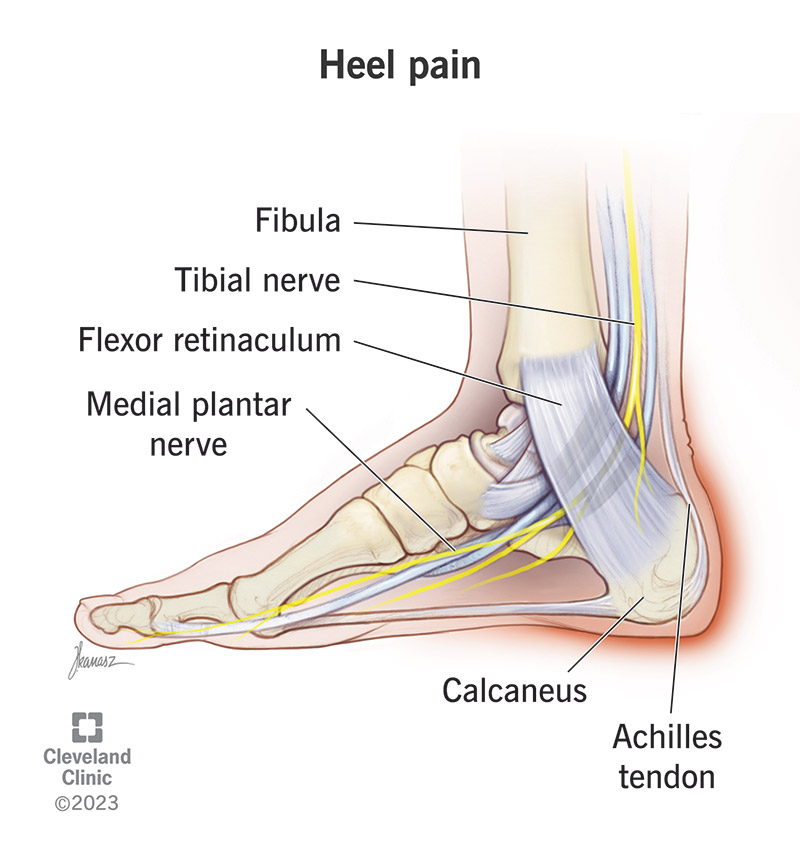

Heel Pain Causes Treatment and Prevention top, Do You Wake Up In The Morning With Excruciating Pain In Your Heels Sutherland Podiatry top, Causes of Morning Heel Pain in Arizona Fixing Feet PLLC top, Why Do I Have Heel Pain in the Morning SPORT Orthopedics top, Why Do I Have Heel Pain in the Morning Here s How to Relieve the Pain Feet Feet top, 5 Reasons You May be Experiencing Foot Pain in the Morning Foot and Ankle Group top, Why do my feet hurt when I wake up and walk top, Foot Pain In The Morning Causes Treatment top, Why Do My Heels Hurt in the Morning Northeast Foot and Ankle top, Heel Pain After Waking Up in the Morning Dr. Chetan Oswal Pune top, Early morning heel pain causes remedies prevention top, Heel Pain in the Morning Here s What It May Mean Advanced Foot Ankle Center Podiatry top, Heel Pain Plantar Fasciitis is a common and Painful Condition top, Heel Pain Causes Diagnosis Treatment top, Why Pain From Plantar Fasciitis Is Worse in the Morning top, Why does my heel hurt when I get up in the morning Catching Health with Diane Atwood top, The Consequences of Leaving Plantar Fasciitis Untreated Plantar Fasciitis top, It Hurts to Put Pressure on My Feet in the Mornings Premier Podiatry top, Plantar Fasciitis Orthopaedic Foot Ankle Surgeon Edinburgh Mr. H Shalaby top, Causes of Morning Heel Pain Blog top, The Do s and Don ts of Plantar Fasciitis Lucky Feet Shoes top, Pioneer Podiatry top, Why Plantar Fasciitis Feels Worse in the Morning Washington Foot Ankle Sports Medicine Podiatry top, How to Treat Your Morning Heel Pain at Home in 3 Easy Steps Foot Leg Centre top, Plantar Fasciitis Causes Symptoms Treatments and More top, Plantar fasciitis Plantar fasciitis is caused by aseptic inflammation of the plantar tendons or fascia. The most common symptoms are heel pain and discomfort often at the heel of the foot sometimes top, Heel pain or plantar fasciitis Treatment exercises and causes top, 4 Heel Pain Symptoms to Take Seriously Chicagoland Foot and Ankle Board Certified Foot and Ankle Specialists and Surgeons top, Plantar fasciitis Symptoms and causes Mayo Clinic top, What is Plantar Fasciitis Common Causes of Plantar Fasciitis top, Common Causes of Heel Pain top, Plantar Fasciitis and Bone Spurs OrthoInfo AAOS top, Plantar Fasciitis Symptoms and Treatment familydoctor top, 2 Major Causes of Heel Pain Leading Edge Physiotherapy St Albert Edmonton Physical Therapy top, Why Heel Pain Won t Disappear Foot and Ankle Podiatrists top.

Heel pain worse in morning top